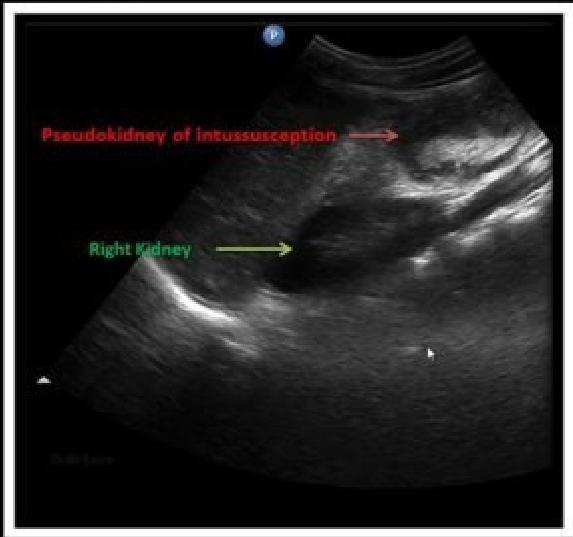

- â Pseudkidney sign

- Pseudokidney sign: This âpseudokidneyâ is made up of longitudinal layers of bowel wall.